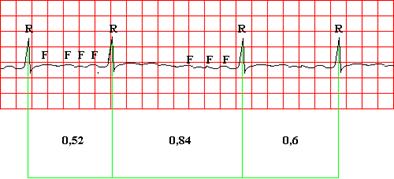

ЭКГ-признаки мерцательной аритмии:

- отсутствуют зубцы Р во всех электрокардиографических отведениях, вместо них регистрируются волны f. Волны f лучше регистрируются в отведениях V1, V2, II, III и aVF,

- нерегулярность желудочковых комплексов QRS (различные по продолжительности интервалы R-R),

- наличие комплексов QRS, имеющих в большинстве случаев нормальный неизменный вид без деформации и уширения.